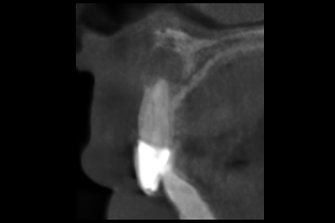

上唇の腫脹を認め、CT検査にて根尖部に嚢胞様透過像を認めた。左上の前歯が不自然に大きく噛み合わせが強くなっていたことがフレアアップの一因と考える。精密根管治療を行い、感染経路を遮断したのち歯根端切除術にて嚢胞を摘出した。

治療中